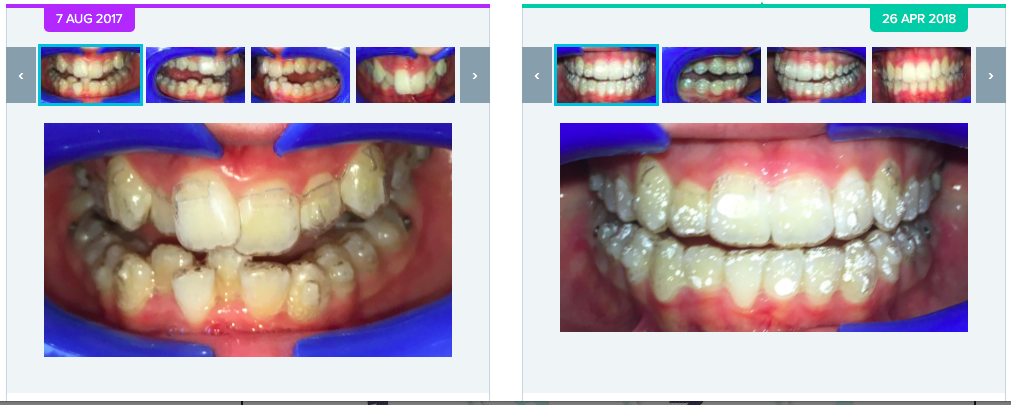

AI can be used to monitor treatment progress and track it against the proposed treatment plan and tooth movements. One of the current ways of incorporating this in your orthodontic practice is to use Dental Monitoring. Our internal clinical practice data from CCC Smiles in 2017 (n=125) shows on average AI technology has saved us 25% in number of appointments scheduled for those patients in comprehensive orthodontic treatment. Interestingly, there was no reduction in the number of appointments per patient for limited orthodontic treatments ranging from 3-9 months and an 15% increase in appointments scheduled for patient with fixed appliances! This study is a pilot and now ongoing for future publication.

AI can be used to monitor treatment progress and track it against the proposed treatment plan and tooth movements. One of the current ways of incorporating this in your orthodontic practice is to use Dental Monitoring. Our internal clinical practice data from CCC Smiles in 2017 (n=125) shows on average AI technology has saved us 25% in number of appointments scheduled for those patients in comprehensive orthodontic treatment. Interestingly, there was no reduction in the number of appointments per patient for limited orthodontic treatments ranging from 3-9 months and an 15% increase in appointments scheduled for patient with fixed appliances! This study is a pilot and now ongoing for future publication.

Do orthodontic treatments finish faster with AI? Treatment times depend on a number of factors and all virtual treatment monitoring detects is progress, breakages and aligner fit (tracking) against the proposed treatment plan. If all other factors are favourable, we should see a reduction in aligner unseats and be able to assess breakages quickly. Our pilot data shows aligner patients are more compliant with prescribed wear time when AI technologies are used – the compliance rose from 50% to 90%. This shows that we should be f

inishing treatments earlier and more predictably. This is yet to be shown in a clinical trial.